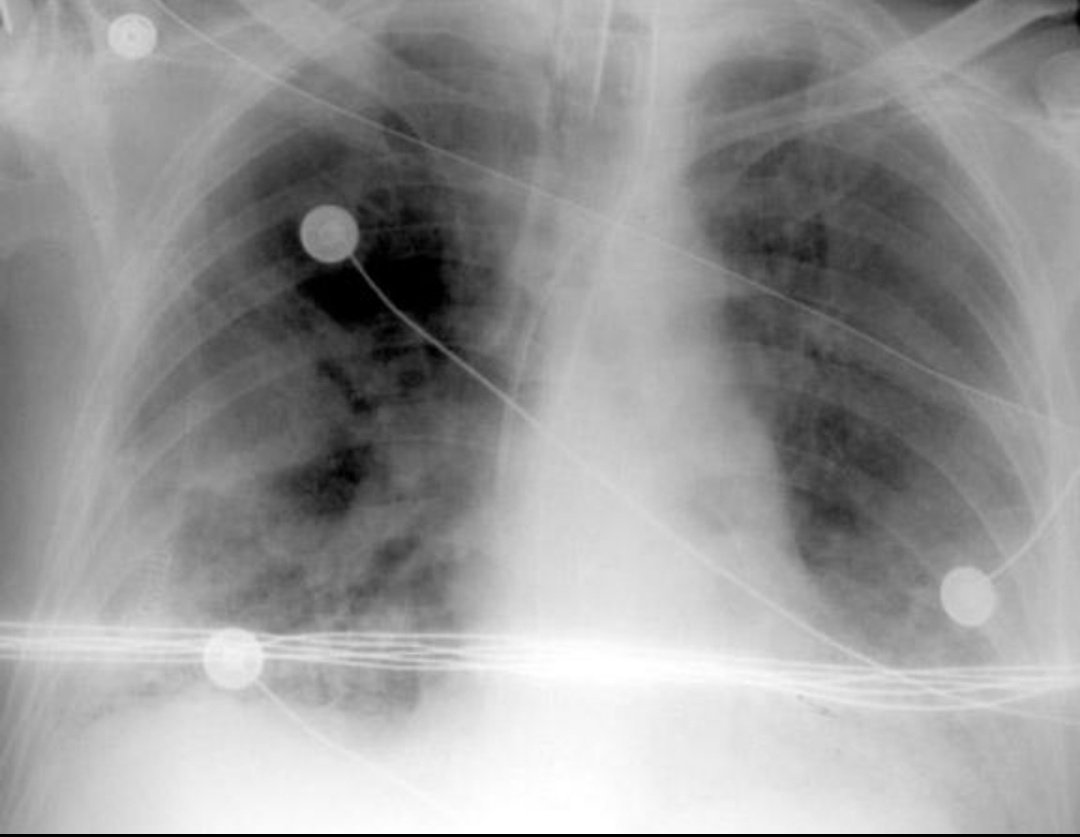

باقي ال ١٧% من الحالات بحتاجو علاج في المستشفى وديل البكونو وصلو مرحلة الإلتهاب الرئوي Pneumonia

عموما الإلتهاب الرئوي مرض خطير وقد يؤدي للوفاة مهما كان سببه سواء فيروسي زي الكورونا أو بكتيري أو فطري أو كيميائي نتيجة استنشاق أبخرة معينة أو نتيجة لمرض مناعي

من المضاعفات الخطيرة حاجة اسمها ARDS

بيحصل ضرر لخلايا الرئة وبتفقد القدرة على أداء وظيفتها لأسباب كتيرة منها إنو بيتكون سائل بين الخلية والأوعية الدموية البتنقل الأكسجين زي الورم البيحصل بعد قرصة حشرة بس طبعا بصورة أكبر وأخطر

بيحصل ضرر لخلايا الرئة وبتفقد القدرة على أداء وظيفتها لأسباب كتيرة منها إنو بيتكون سائل بين الخلية والأوعية الدموية البتنقل الأكسجين زي الورم البيحصل بعد قرصة حشرة بس طبعا بصورة أكبر وأخطر

والمهم جدا (وقد يكون منقذ للحياة) ومعروف وموجود في البروتوكولات العلاجية لأنو بخفف التورم وبيثبط الجهاز المناعي من إنو يفرز مواد تزيد من حالة الضرر على الأنسجة في الرئة وأعضاء أخرى زي الكلى